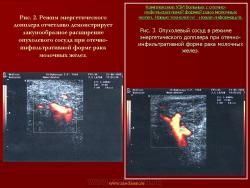

Комплексное ультразвуковое исследование молочных желез.